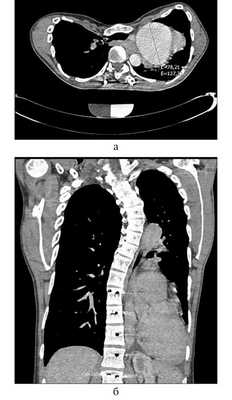

По данным компьютерной томографии (КТ): грудная клетка воронкообразной формы. Органы средостения смещены влево от срединной линии, соответственно изгибам позвоночника (рис. 2). Сердце располагается в левой половине грудной полости. При внутривенном болюсном контрастировании определяется аневризма корня аорты до 70 мм, диаметр восходящего отдела аорты 33 мм, дуги 35 мм, нисходящего отдела 27 мм. В области левого коронарного синуса определяется локальная диссекция интимы. Грудной отдел позвоночника с признаками кифосколиоза. Левый главный бронх зажат между изгибом позвоночного столба и грудным отделом нисходящей аорты, щелевидной формы, стеноз около 90%.

Рис. 2. МСКТ органов грудной клетки. а — аксиллярный срез с гигантской аневризмой аорты; б — фронтальный срез, сердце в левой плевральной полости.